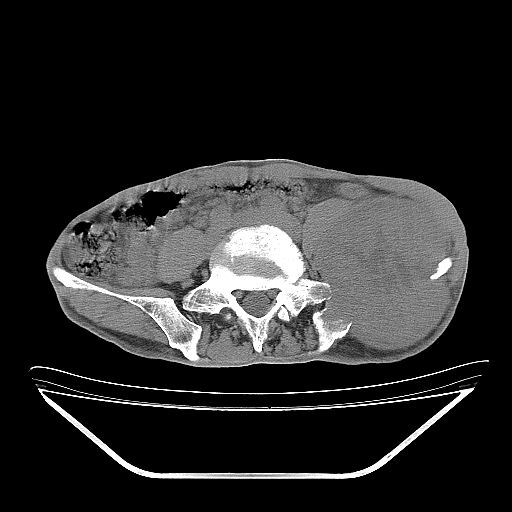

以下是引用天南地北在2007-10-4 18:01:00的发言:[br][br]考虑左髂部恶性肿瘤(溶骨性骨质破坏+软组织肿块影+残留骨质);以滑膜肉瘤可能性大。[br]建议穿刺活检

以下是引用liuyue在2007-10-4 23:38:00的发言:[br]左髂部恶性肿瘤,建议穿刺活检,或先做肺部检查,除外肺癌转移之可能。